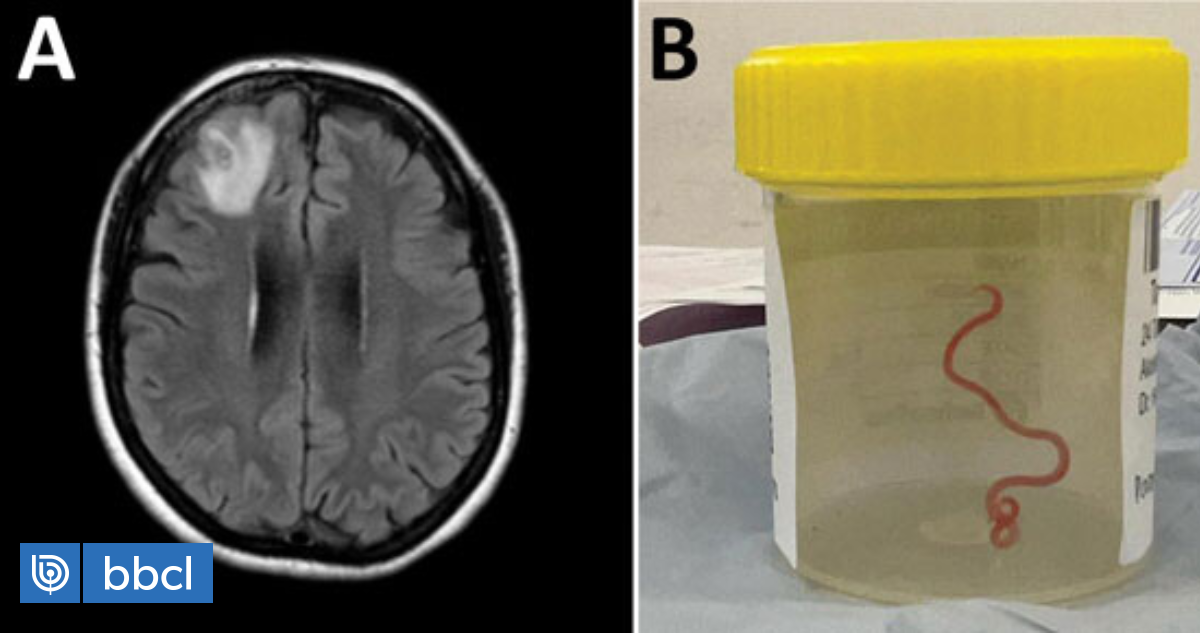

En 2022, la mujer se sometió a una resonancia magnética tras experimentar trastorno de memoria y depresión. Las imágenes que arrojó la resonancia de su cerebro revelaron que la mujer tenía una lesión atípica en el lóbulo frontal derecho.